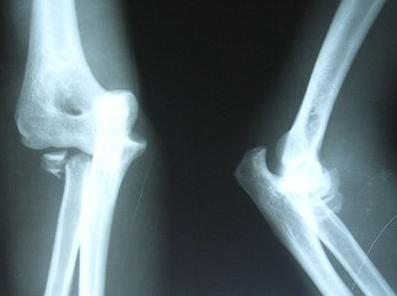

骨不连是属于骨折后的并发症,骨折端位不好,受到药物的刺激,过度的牵引,严重开放性骨折,软组织损伤较大,血管受损伤挤压造成患部血运不良,骨组织感染,内固定材料过敏等,只要达到一定的时间强度的刺激,都会产生一系列的神经、内分泌、免疫功能的改变而引发骨不连。

骨不连只是骨髓炎发生时的一种情况,但是不是同一种疾病,骨不连在治疗不及时会转变成骨髓炎,这时需要引起人们的重视的。再骨折手术治疗的过程中,如果出现延迟愈合或是骨不连时,就要好好研究一下真正的病因所在。

这里不得不提的是手术因素,因手术本身就具有创伤性,会造成骨折周围软组织破坏,由于本身的抵抗力下降,加上手术过程中不关注防止细菌性感染,造成骨折端易受感染的因素更大,如果正好是由于细菌引起的骨不连,就会出现骨髓炎跟骨不连同时发生,如果不是由于细菌感染引起的骨不连,而是术后呈现骨不连的情况,由于时间长,周围组织形不成很好的防御功能,在治疗上不及时而转变成慢性骨髓炎。